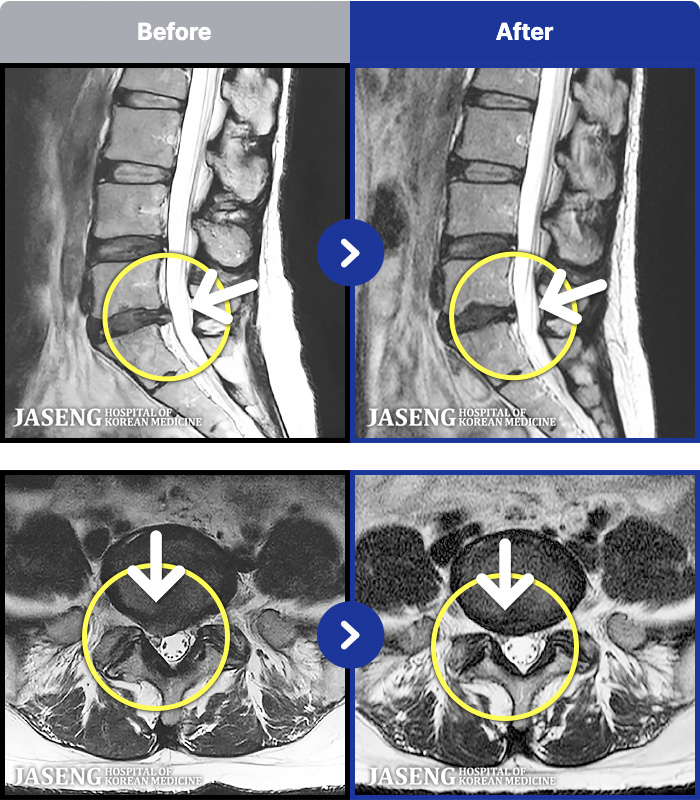

MRI ġ

1,304 MRI ũ ʸ Ȯϼ.